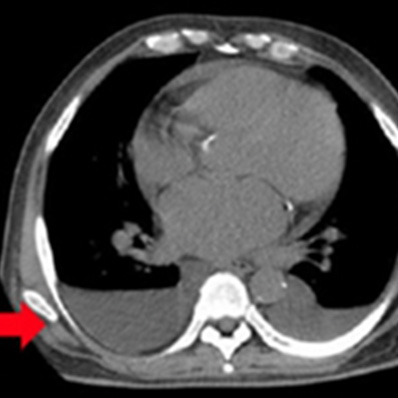

外傷性気胸

肺挫傷

急性大動脈解離

(StanfordA型)

外傷性血胸